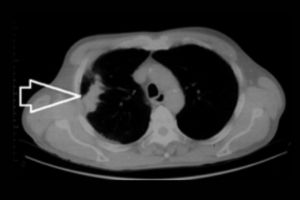

What is a CT Head and Left Orbit scan?

A CT Head and Left Orbit scan is a specialised imaging test that uses computed tomography (CT) technology to produce detailed cross-sectional images of the head and the left eye socket (orbit). This scan helps evaluate the bones, brain, soft tissues, and structures within and around the left eye. It is commonly used to detect abnormalities such as fractures, tumours, infections, bleeding, or foreign bodies in specified areas. The test is non-invasive and may involve the use of a contrast agent to enhance the visualisation of blood vessels and specific tissues. It is often ordered in cases of trauma, neurological symptoms, or eye-related concerns.

- To detect fractures or bone abnormalities in the skull or orbit after trauma.

- To identify tumours, masses, or cysts in the brain or eye socket.

- To evaluate for bleeding, swelling, or ischemia in the brain.

- To locate and assess foreign bodies in or around the left eye.

- To diagnose infections or inflammatory conditions affecting the brain, orbit, or sinuses.

What can CT Head and Left Orbit detect?

A CT Head and Left Orbit can detect fractures, tumours, infections, bleeding, and other abnormalities in the brain, skull, and eye socket.